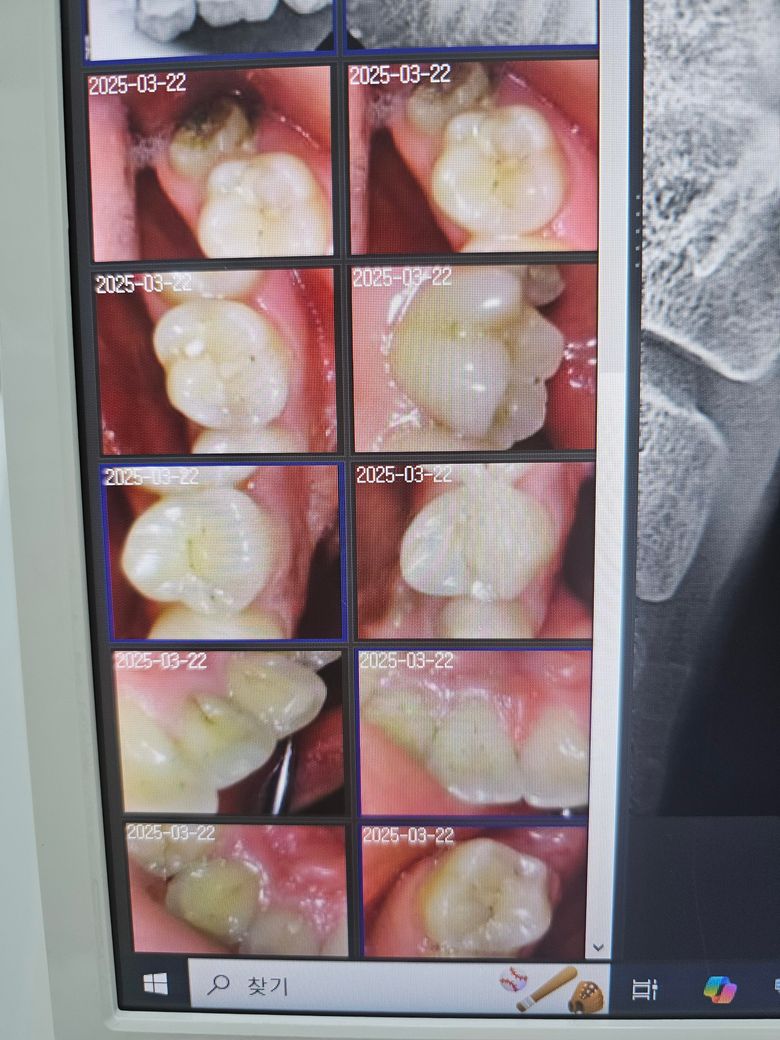

인접면충치 전문가분들의 의견이 궁금합니다

전문가분들이 보시기에 어떤것같나요?

두번째 치과에서 하신 말씀이랑 다들 비슷한 의견일꺼에요. 치과의사마다 치료 하는 방법이 다르기 때문에 어떤게 옳다고 말씀드리기가 어렵습니다. 사진상으로 인접면에 충치가 없는건 아니고 의심되는 치아들이 많이 보이긴하니 계속해서 의심이 드신다면 불편한 치아만 치료를 먼저 하시고 나머지는 지켜보시면될것같습니다.

사진으로만 보기에는 큰충치가 보이지는 않습니다.

• 4번 째 사진

• 5번 째 사진

• 6번 째 사진

• 7번 째 사진

• 8번 째 사진

• 9번 째 사진

• 10번 째 사진